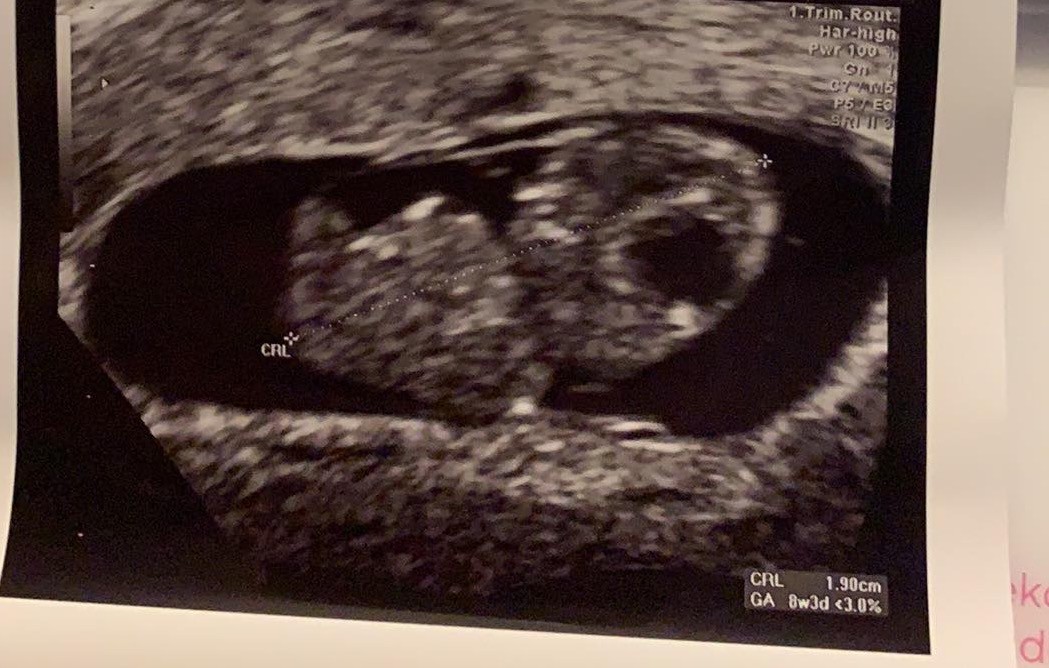

Długo mnie tutaj nie było ze względu na ciagle mdłości i sen, ale dzisiaj byłam na wizycie i słyszałam pierwszy raz serduszko mojego maleństwa i stwierdziłam, że koniecznie muszę się Wam pochwalić ❤ 8+3, termin na 11 stycznia a jutro umawiam się na początek lipca na prenatalne 😊Zobacz załącznik 1128859

Super że dodałaś zdjęcie, mam pogląd jak mój dzidziuś aktualnie wygląda ♡ pozdrawiam Cię, rzeczywiście dawno Cię tu nie było...